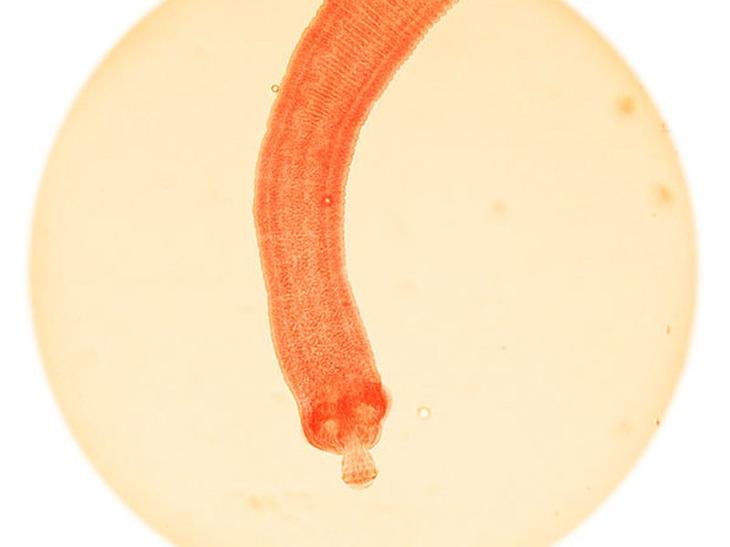

Солитеры, или ленточные черви, — 700 смертей в год

От цистицеркоза, которым заражаются от этого паразита, ежегодно погибает около 700 человек.

Аскариды — 4500 смертей в год

Согласно исследованию 2013 года, аскариды вызывают болезнь под названием аскориаз, которая ежегодно убивает примерно 4500 человек. ВОЗ отмечает, что заражение происходит в тонком кишечнике людей и это заболевание больше поражает детей, чем взрослых.